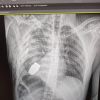

Операція під наглядом саперів: з тіла бійця ЗСУ дістали гранату ВОГ, що не розірвалася

☝️ Операція проводилася одним з найдосвідченіших хірургів ЗСУ – Андрієм Вербою без електрокоагуляції, оскільки граната могла детонувати у будь-який момент.

Військовослужбовця було відправлено на подальшу реабілітацію та відновлення.